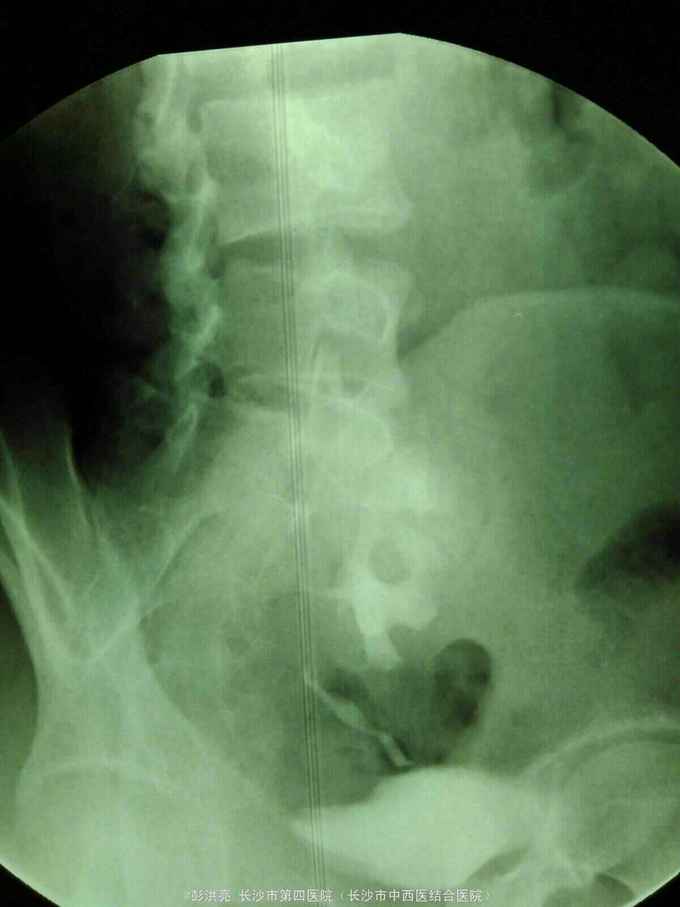

男性,25岁,左腰痛入院。2年前在外院发现左侧盆腔异位肾并肾盂输尿管移行处结石行腹腔镜下切开取石术。现CT示左侧盆腔异位肾并多发结石。术前其他检查正常。

请问该患者如何处理。